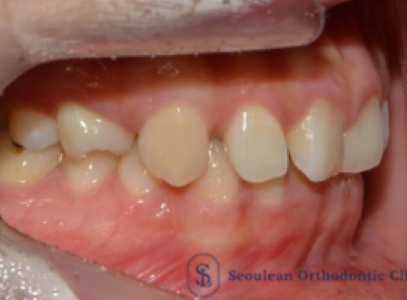

분당 판교 교정치과|10대 여학생 심한 덧니·중심선 편위, 선천적 결손치 발치교정 치료 사례